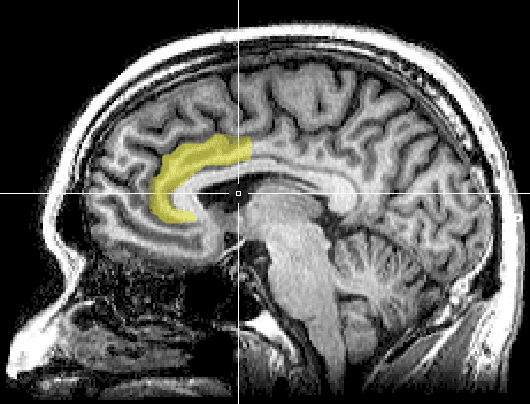

Highlighted region shows the anterior cingulate cortex, a region of the brain shown to be activated during meditation. Image by Geoff B Hall